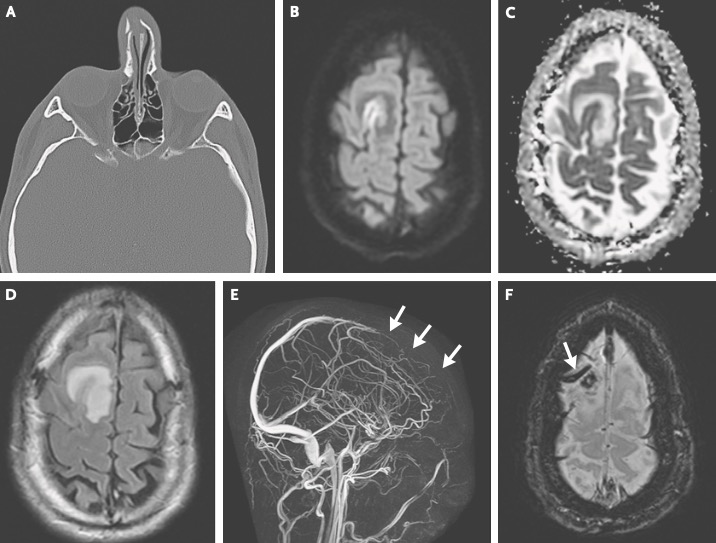

虽然初步的神经系统体格检查并无异常,但阿峰的脑核磁结果却明确显示上矢状窦前部和右额叶凸面皮质静脉各有一枚血栓,右额上回皮层和右额叶白质出现了明显水肿。

图源:参考资料 15

这极有可能就是他反复癫痫发作的原因。